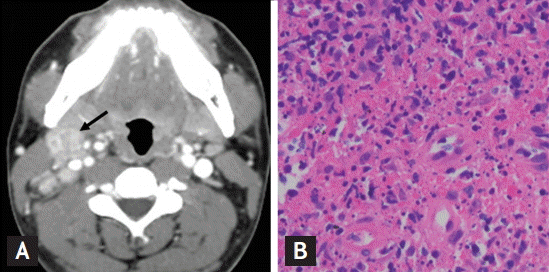

Computed tomography (CT) scan of the neck revealed multiple enlarged lymph nodes at all cervical levels on the right side without evidence of abscess formation (Fig. 1A). Abdomen, pelvis, and chest CT scans and plain chest radiography revealed no abnormal findings except for a small pericardial effusion. Pathologic findings from ultrasound-guided core needle biopsies of nodes revealed necrotizing lymphadenitis, which was histologically compatible with KD (Fig. 1B) and polymerase chain reaction was negative for Mycobacterium. The patient was put on levothyroxine 100 μg/day, was treated symptomatically for fever, and lymphadenopathy resolved spontaneously. In addition, all abnormal laboratory findings and pericardial effusion had normalized after 2 months.

Figure 1.

(A) Contrast-enhanced computed tomography of the neck showed enlarged right cervical lymph nodes (arrow). (B) Lymph node biopsy demonstrated mixed inflammatory cells including histiocytes and plasmacytoid monocytes with necrotic fibrin debris and karyorrhexis (H&E, ×400).